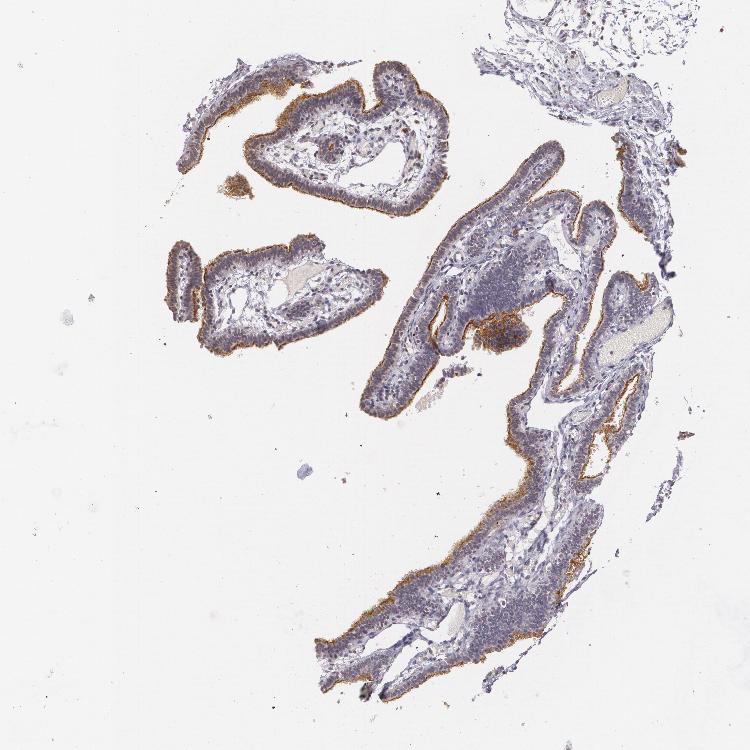

TISSUE PRIMARY DATA FALLOPIAN TUBE Show tissue menu

FALLOPIAN TUBE - Antibody stainingi

Antibody staining in the annotated cell types in the current human tissue is reported as not detected, low, medium, or high, based on conventional immunohistochemistry profiling in selected tissues. This score is based on the combination of the staining intensity and fraction of stained cells.

Each image is clickable and will lead to virtual microscopy that enables deeper exploration of all samples and also displays staining intensity scores, fraction scores and subcellular localization as well as patient and tissue information for each sample.

Antibody HPA004179Antibody HPA007235Antibody HPA008855Antibody CAB000036Antibody CAB001986Antibody CAB080102Antibody CAB080103

Glandular cells HighMediumHighHighMediumHighHigh